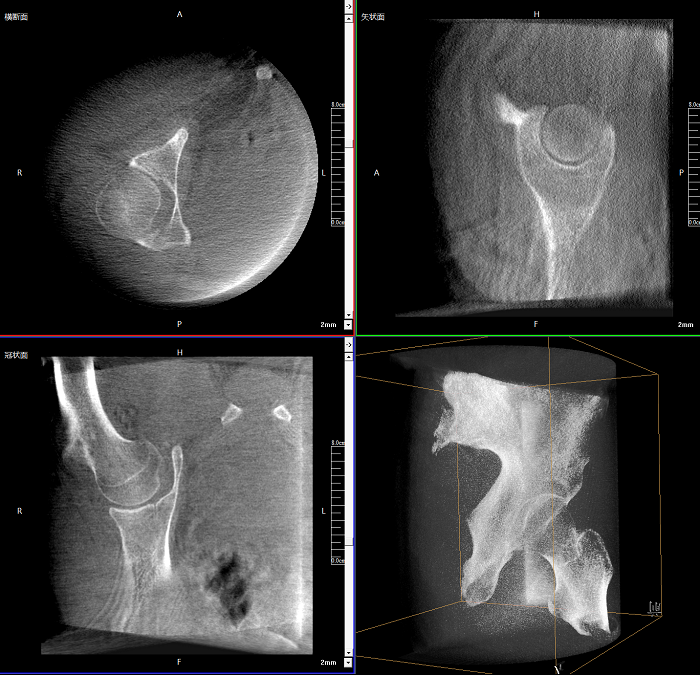

三維成像 全面觀察

任意視角、任意切面觀察

術中實時生成橫斷面、矢狀面、冠狀面及三維影像,可在任意切面、任意角度評估植入物和解剖結構的相對位置。

Clinical picture

臨床圖片